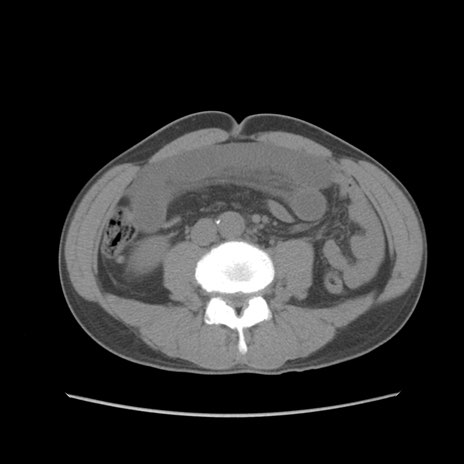

症例56 CT(横断像)

脂肪ウインドウ